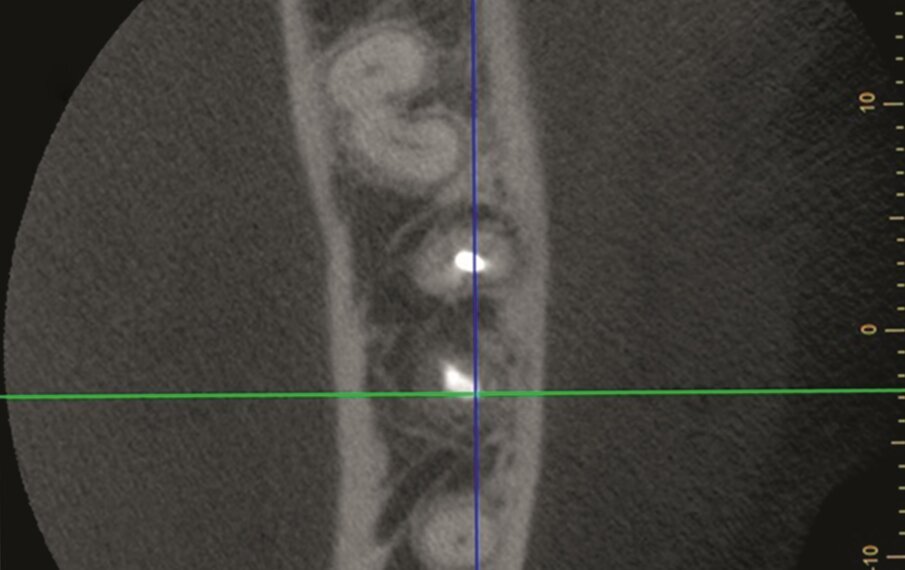

A 63 year old female patient, with a non-contributory medical history, consulted owing to moderate pain associated with her previously treated mandibular left first molar. CBCT revealed that a mesiobuccal canal had being missed during initial treatment, that the mesial and distal roots were affected by an apical lesion, and that the cortical buccal bone was intact.

Retreatment was done in two appointments, and calcium hydroxide was used as the intra-canal dressing after removing the previous filling material and cleaning and shaping three canals. After one week, root canal therapy was completed. Two months later, symptoms persisted and clinical examination revealed pain on vertical percussion; periodontal probing depth and mobility were within normal limits. CBCT revealed no signs of bone healing (Figs. 1a–c). The diagnosis for tooth #36 was previously treated symptomatic periapical periodontitis, and the treatment of choice was guided EMS.

An intra-oral scan (TRIOS, 3Shape) of the mandible, and the resulting STL file was combined with the DICOM files of the CBCT scan to plan a surgical guide using the Blue Sky Bio software. A template that marked the limits of a cortical window to accurately reach the apical area was designed and printed (Fig. 1d).